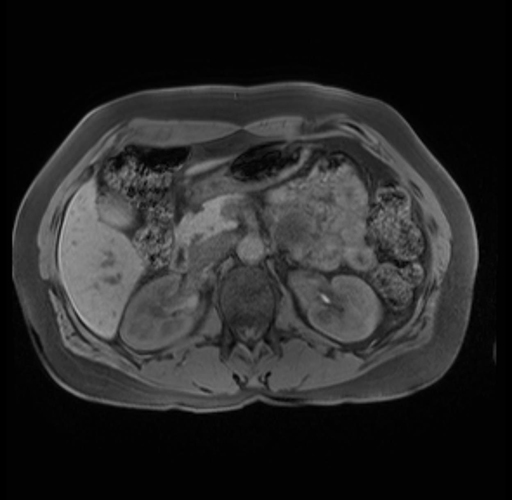

Imaging Analysis

Look through the patient's CT scan to identify any areas of concern for the necessary procedure.

Based on your CT findings, which issue(s) are present and would give reason for "planned slowing down moment(s)" in this case?